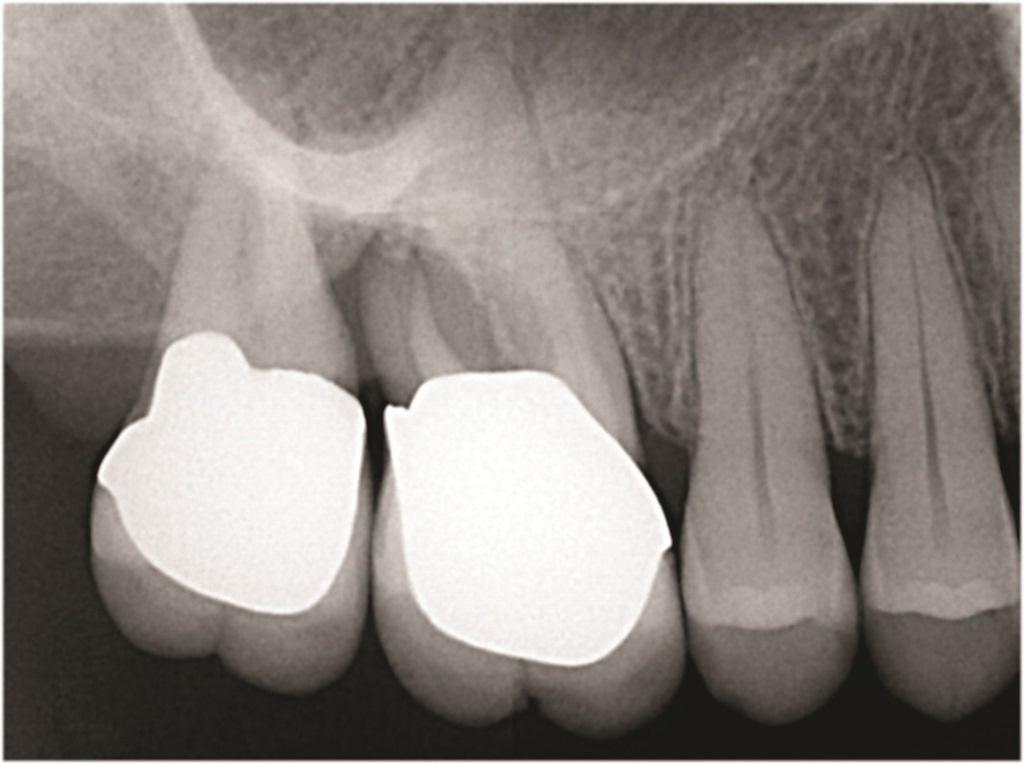

К таким патологическим состояниям относятся вертикальные переломы корней, перфорации корней, пародонтит с поражением корней из-за проблем в области фуркации или сближения корней, сочетанные эндодонтическо-пародонтальные дефекты на фоне коротких корней, устойчивые фуркационные дефекты, значительные не поддающиеся лечению внешние резорбтивные дефекты и другие (Фото 1–4). Когда подобные состояния затрагивают однокорневые зубы, удаление часто является единственным способом устранения патологии. Однако в случае многокорневых зубов существует дополнительная возможность: полное удаление источника патологии с одновременным сохранением функциональности зуба, что демонстрирует опубликованные показатели выживаемости на уровне 80–90%. При правильном выполнении с учетом описанных в статье факторов такое функциональное состояние может сохраняться в долгосрочной перспективе со средним сроком службы от 6 до 20 лет.

Фото 1: Зуб 1.6 с дистально-щечным корнем, демонстрирующим циркулярную потерю кости от уровня краевой кости до верхушки при стабильных мезиально-щечном и небном корнях.